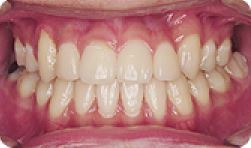

임플란트 전후사례 | 2020.03.06 |